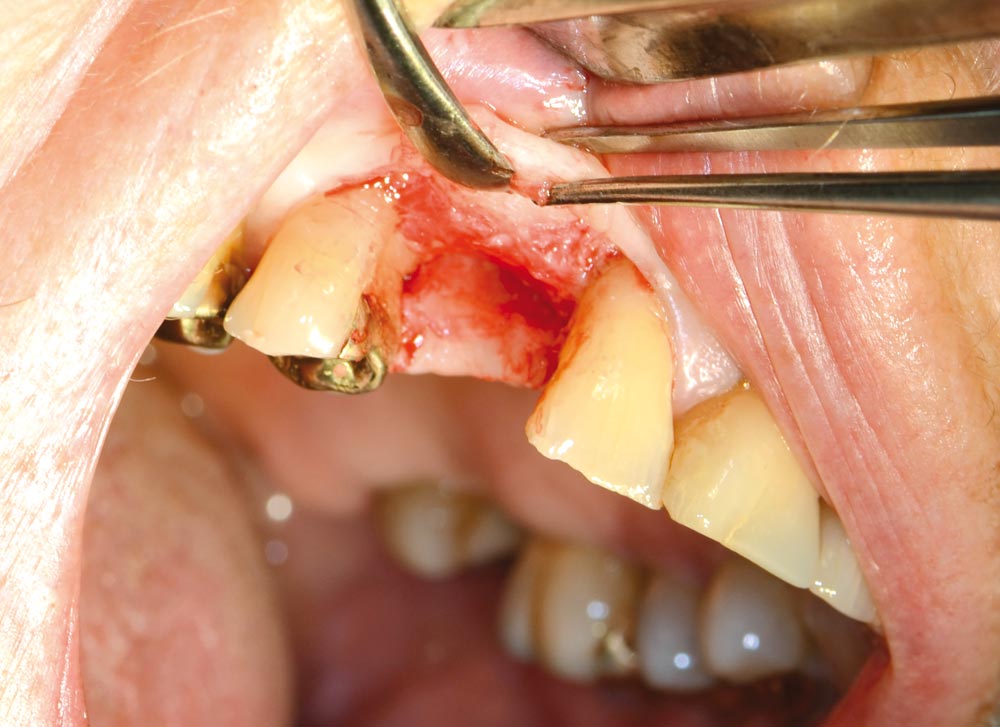

05/12 - Intraoperative situation

Block augmentation with maxgraft® in the maxilla - PD Dr. Dr. F. Kloss